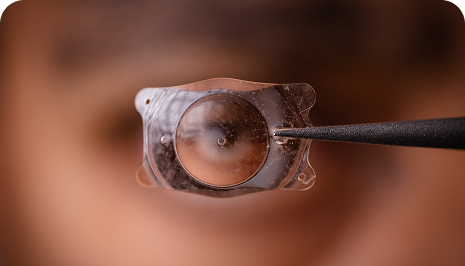

ICL Surgery

What is ICL Eye Surgery? ICL or Implantable Collamer Lens surgery is a type of refractive surgery, in which an artificial lens is implanted in